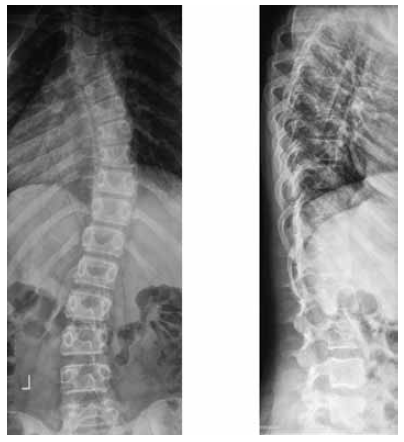

Over the next 3 years, the pediatric patient was supervised with a spinal support, and the previous mode of wearing an orthosis was observed. Moreover, the patient underwent control examinations every 4 months and an imaging study every 6 months, received courses of conservative treatment, back massage (excluding the postoperative scar area), and did swimming. During this period of observation, one more replacement of the spinal support was required, and several additional corrections were performed during the follow-up period. During this period, the growth of the patient had increased by another 3 cm. At the age of 14, the patient had menses, and the height of the child between the ages of 14 and 15 did not change. A stable pattern was clinically observed, as manifested by a symmetrical arrangement of the shoulder girdles and angles of the shoulder blades, the absence of pelvic distortion, and the presence of slight asymmetry of the waist triangles. At the age of 14.5, a gradual withdrawal of the spinal support had started, during which the time spent without spinal support gradually increased, starting from night period. During this time without spinal support, the patient was actively engaged in physical therapy aimed to strengthen the muscles of the back, shoulder girdle, and abdominal tension. In addition, the patient did swimming and received back massage courses. Courses of conservative therapy enabled the patient to completely exclude the spinal support for 6 months. At the age of 15, the control spinal imaging study was performed. On the radiographs, the position of the surgical hardware in the upper thoracic region was correct and stable. There was no loss of the achieved correction of the deformity as compared to that of postoperative period. There was a right-sided scoliotic arch of Th7–Th10 of 5°, and a left-sided scoliotic arch of L1–L4 of 8° (Fig. 5).

Fig. 5. Radiographs of the spine of the patient F., 15 years old, in a standing position without spinal support